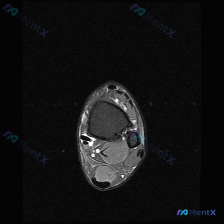

刚整理了一份膝关节MRI读片病例,分享出来和大家一起讨论一下思路。 病例基本影像信息 这是一张膝关节MRI(T2序列)轴位图像,层面覆盖膝关节前部,包含髌骨、股骨滑车及周围软组织结构: - 髌骨:骨皮质信号缺失(低信号),髓腔信号正常,皮质连续性尚可,无明显骨折线 - 股骨滑车:位于髌骨后方,可见内...

今天看到一份很有警示意义的膝关节MRI读片病例,整理出来和大家分享一下。这是一份经过髌股关节区域的膝关节轴位T2加权MRI,原始问题提示观察「软骨异常」,我们先把影像所见整理清楚: 一、病例基本影像信息 1. 髌股关节区域:髌骨前方及关节周围软组织可见弥漫性高信号,符合水肿/炎性渗出表现;髌股关节外...